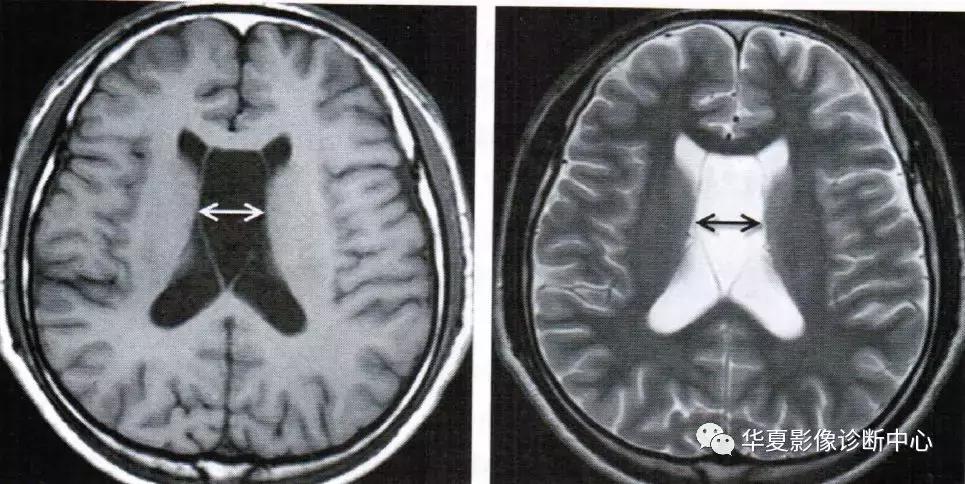

上图为透明隔囊肿

透明隔囊肿表现为透明隔两侧壁弯曲甚至膨隆,失去正常平行状态,且侧壁间距>10mm